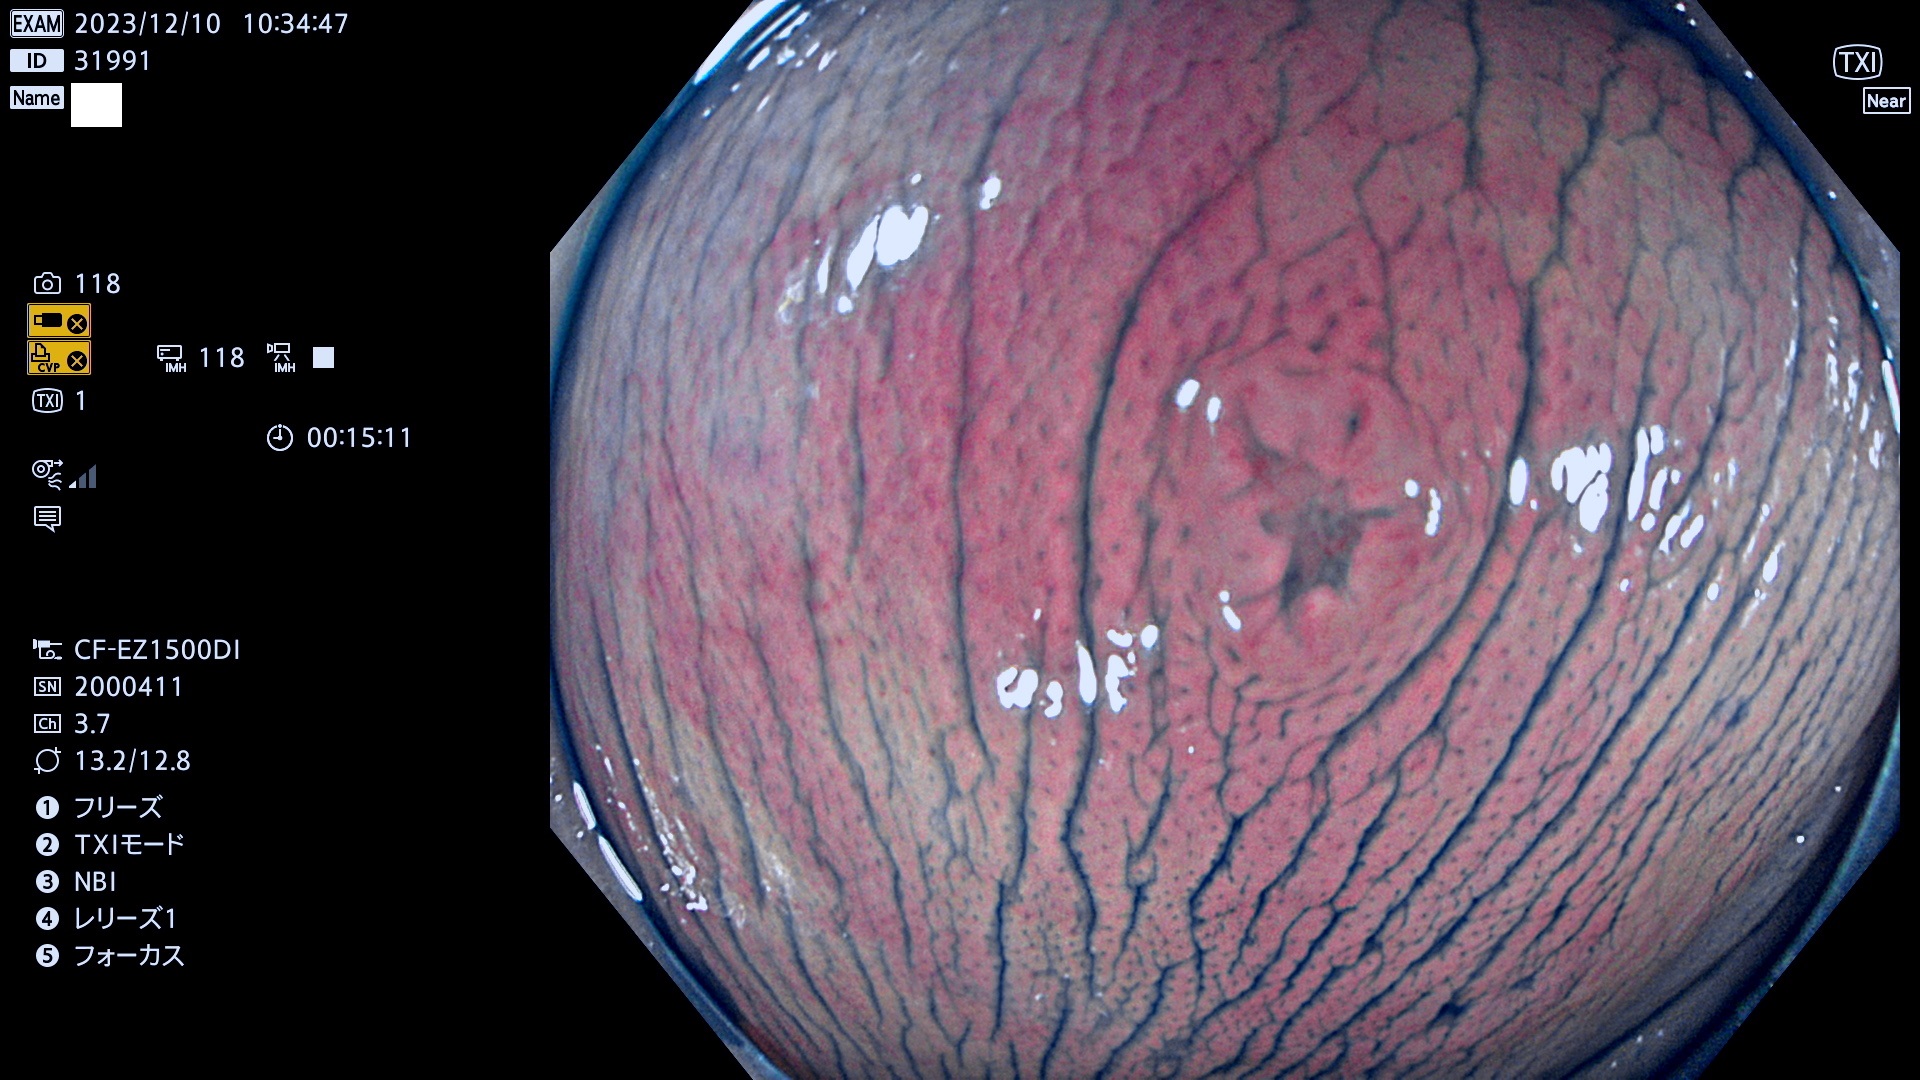

表面型腺腫(Flat Adenoma)の中で、完全に平坦な物をUb、陥凹している物をUcと呼びます。平坦隆起型(Ua)よりも、発見が難しく危険な病変です。このタイプは「内視鏡後・大腸癌の重要犯人」であり、この発見率は「腺腫発見率」よりも、重要な意味があります。

毎週の検査(木・金・土・日)に発見されたUb、Uc型・腺腫を、その週の日曜の夜にUPし1週間、提示します。

抽出の対象期間 2023年12月7日(木)〜12月10(日)の4日間(48件の検査)12件